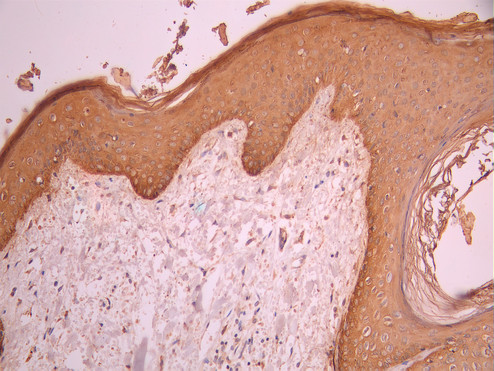

IHC image of CSB-RA557526A0HU diluted at 1:100 and staining in paraffin-embedded human skin tissue performed on a Leica BondTM system. After dewaxing and hydration, antigen retrieval was mediated by high pressure in a citrate buffer (pH 6.0). Section was blocked with 10% normal goat serum 30min at RT. Then primary antibody (1% BSA) was incubated at 4°C overnight. The primary is detected by a Goat anti-rabbit polymer IgG labeled by HRP and visualized using 0.05% DAB.